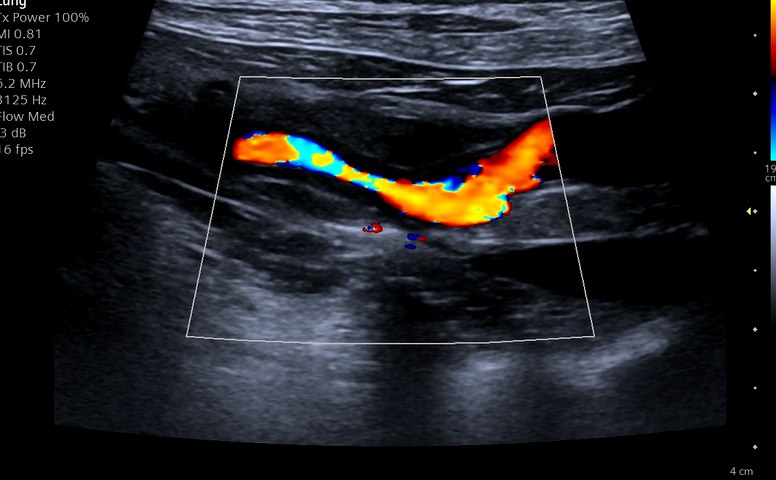

Angioplastia şi Stentarea în Boala Ocluzivă Ateromatoasă a Aortei Infrarenale (patologie extrem de rar întâlnită) la un câine de 16 ani realizată cu succes în premieră în România (şi rar efectuată la nivel internaţional) de către echipa AvantGarde CardioTeam în cadrul Laboratorului de Radiologie Intervenţională Veterinară “Doctor’s Vet Univers” Bucureşti, România.

Angioplasty and Stenting in Atheromatous Occlusive Disease of the Infrarenal Aorta (extremly rare diagnosed pathology) in a 16 years old dog successfully performed for the first time in Romania (and rarely effectuated internationally) by the AvantGarde CardioTeam in the Veterinry Interventional Radiology Laboratory “Doctor’s Vet Univers” Bucharest, Romania.